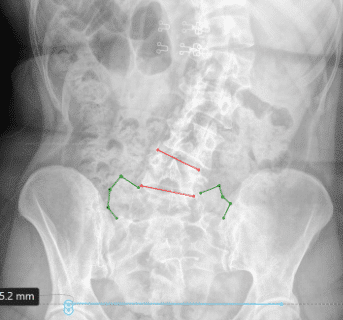

Pelvic obliquity causes the pelvis to become unnaturally tilted, causing one hip to sit higher than the other. Pelvic obliquity can disrupt posture, movement, and cause pain. Common causes include uneven bones in the pelvis, leg length discrepancy, and hip contractures.

Scoliosis causes an unnatural lateral spinal curve, uneven hips, and a lateral pelvic tilt can develop as a result if enough uneven pressure is occurring.